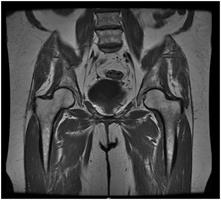

Your doctor has ordered a MRI (Magnetic Resonance Imaging) of your pelvis. MRI uses a magnetic field, radio waves and a computer to create images soft tissues, bones, and internal body structures. MRI of the pelvis allows physicians to examine the pelvic anatomy to rule out any structural abnormalities.